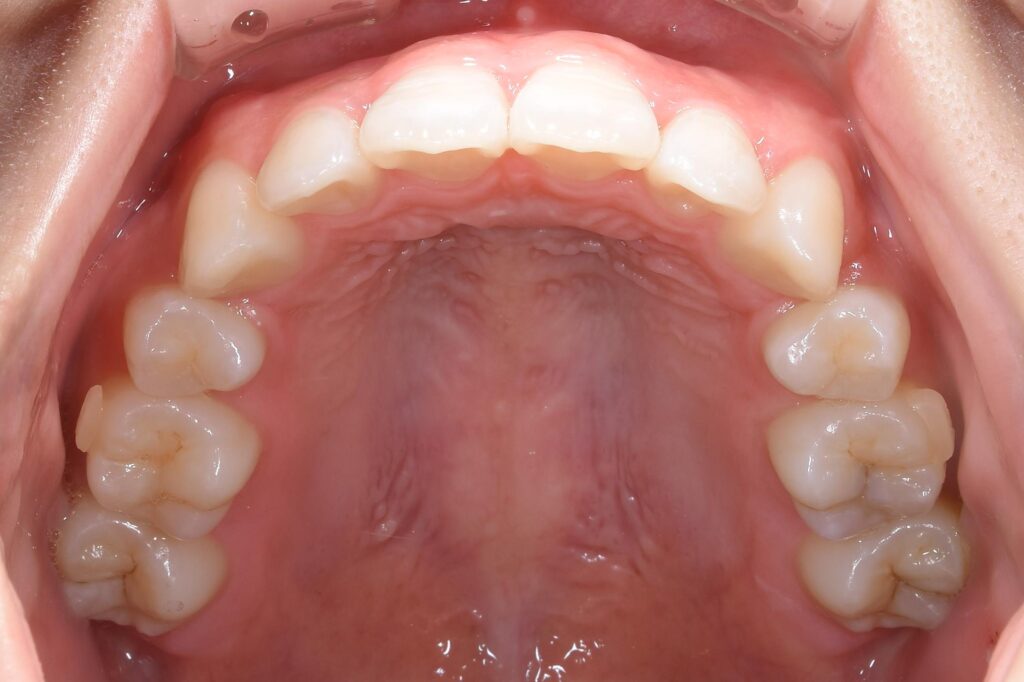

まずは術前の状態をお見せ致します。

【矯正治療前】

いかがでしょうか。

この患者様のお悩みは出っ歯。横からの写真で、出具合が顕著に確認できます。